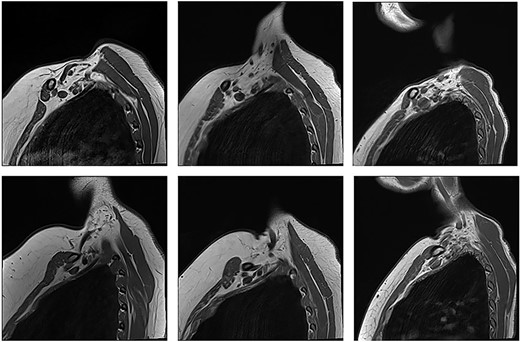

With the arm elevated, there is narrowing of the costoclavicular space between the posterior border of the clavicle and anterior border of the first rib (Figs 1 and 3). In unaffected patients, there is a small amount of fat that persists around the cords of the brachial plexus with the arm elevated (Fig. 2). In our series, we considered a patient to be positive for nTOS if there is loss of the perineural fat signal demonstrating that the nerves are in direct contact with the posterior border of the clavicle and anterior border of the first rib (Fig. 1b).

Unaffected patients. The top row are sequences with the arm in the neutral position. The bottom row is the corresponding patient with the arm raised.